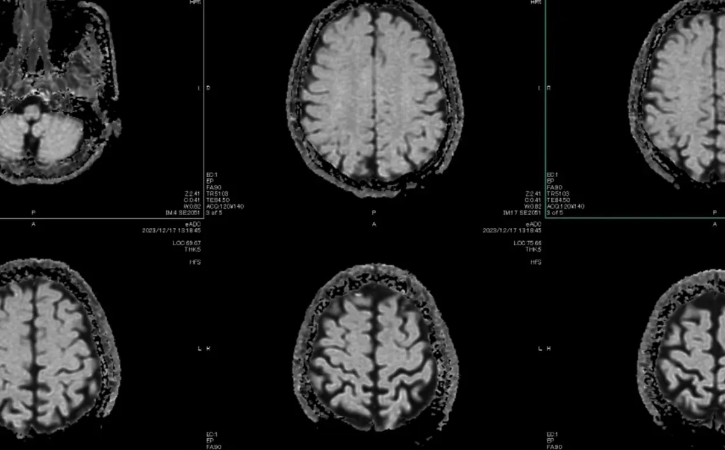

Pothuajse një dekadë më parë, shkencëtari i kompjuterave dhe fituesi i Çmimit Nobel Geoffrey Hinton (i njohur si “Kumbari i AI-së”) tha se spitalet duhet të ndalojnë trajnimin e radiologëve sepse, brenda pesë vitesh, AI do ta bënte punën më mirë. Pothuajse 10 vjet më vonë, ka më shumë radiologë se kurrë. Nga 950 mjetet e inteligjencës artificiale dhe të të mësuarit automatik që morën miratimin e FDA midis viteve 1995 dhe 2024, 723 ishin pajisje radiologjie. Makineritë u përmirësuan. Njerëzit nuk u larguan.

Në disa mjedise, inteligjenca artificiale tashmë po i tejkalon mjekët. Kardiologu dhe studiuesi Eric Topol tregoi pesë studime në të cilat sistemet e inteligjencës artificiale që punojnë në mënyrë të pavarur i tejkaluan mjekët që kishin qasje në inteligjencën artificiale si mjet.